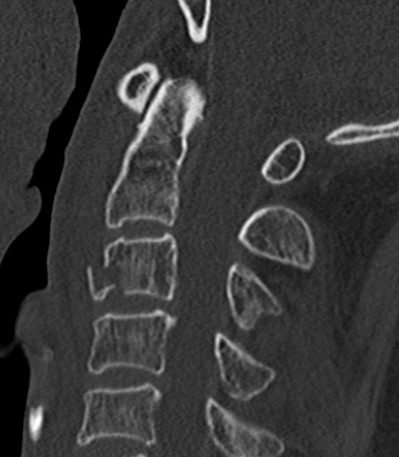

Xray / CT

Large antero-inferior body fragment / tear drop

- > 20 %

- stays attached to ALL

+/- posterior superior fragment retropulsed into canal